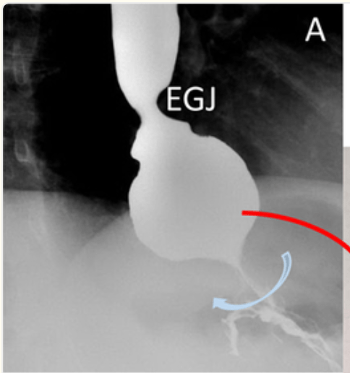

Complication after Nissen fundoplication with this postop barium swallow and EGD view looking at the hiatus

What is a slipped wrap?